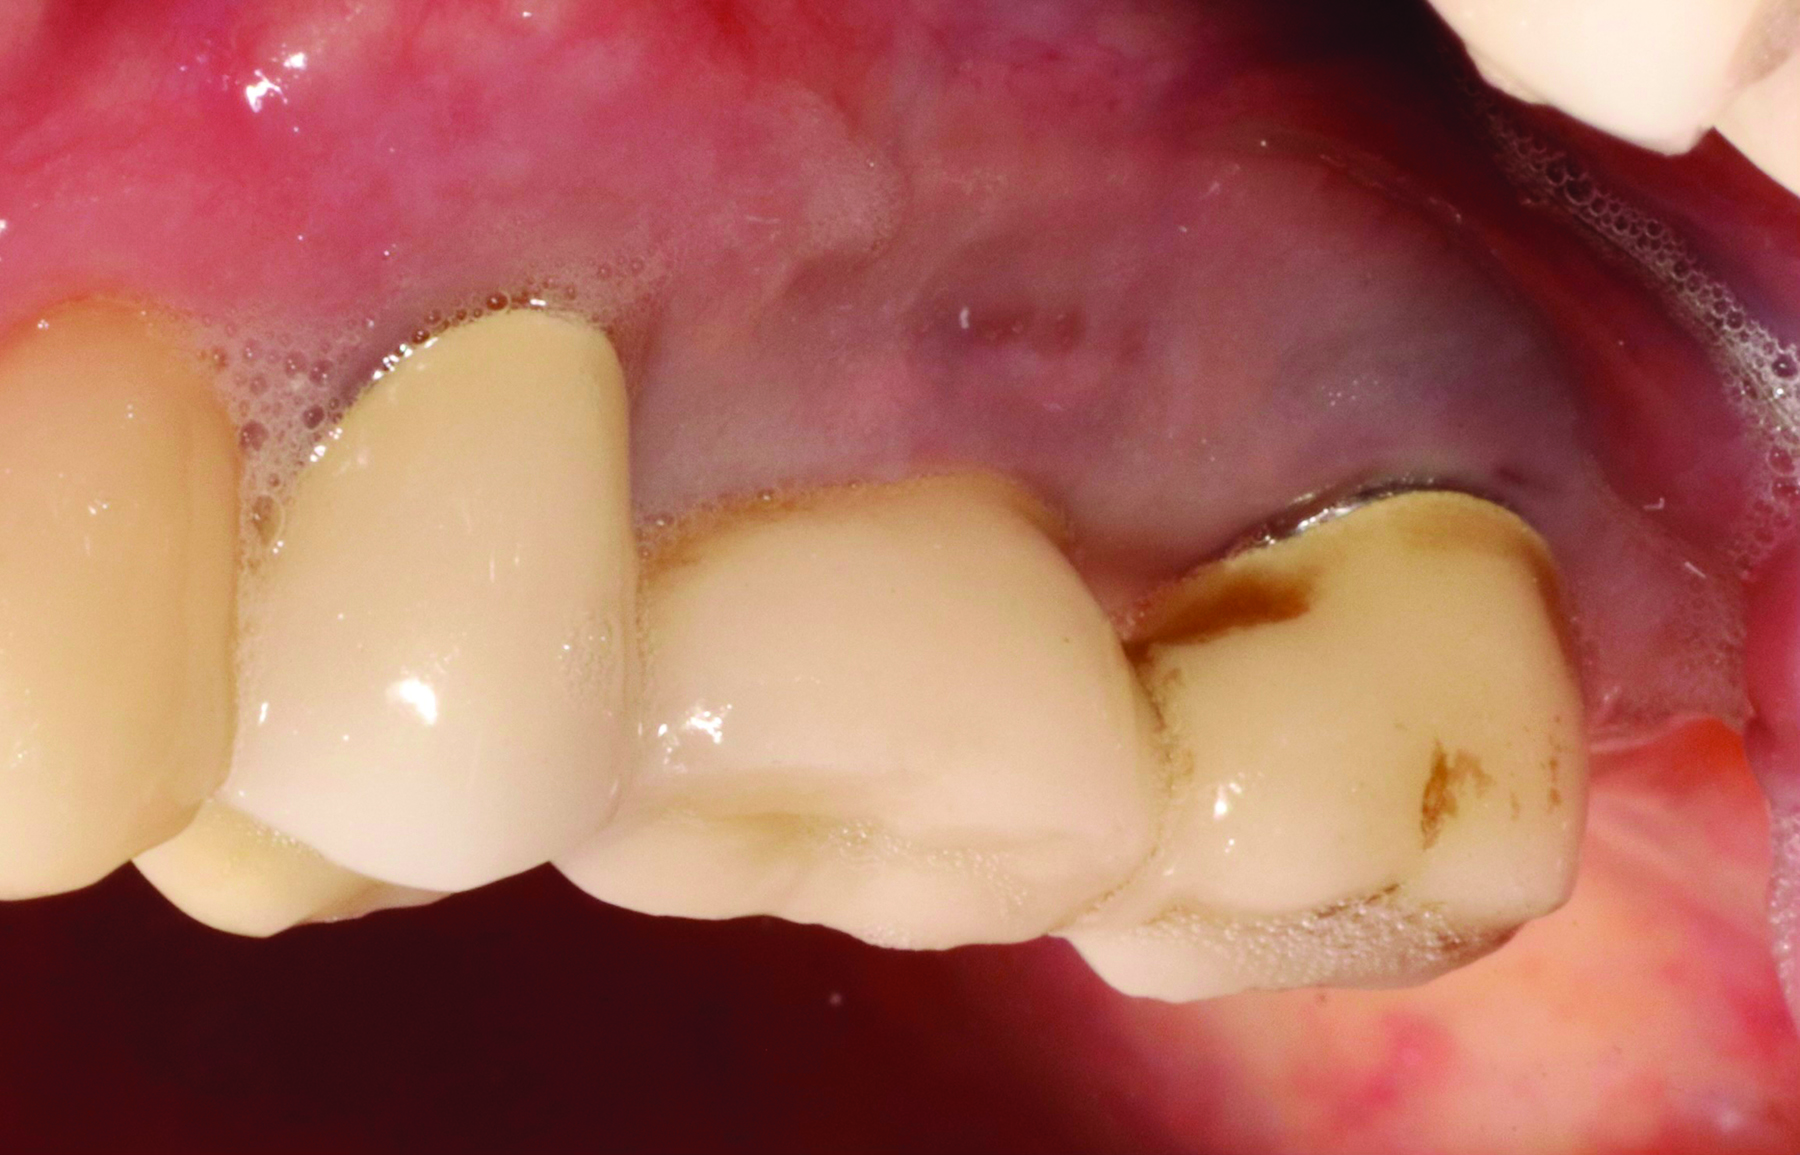

Fig 3 and Fig 4. Pre- (Fig 3) and post-treatment (Fig 4) photographs of a patient who received free gingival grafting at implant sites Nos. 21 and 22. Note the increased amount of keratinized tissue at the areas postoperatively (Fig 4). The patient was placed on 3-month supportive peri-implant care post-surgery and reported increased comfort during her home care regimen.

Figure 3

Figure 4